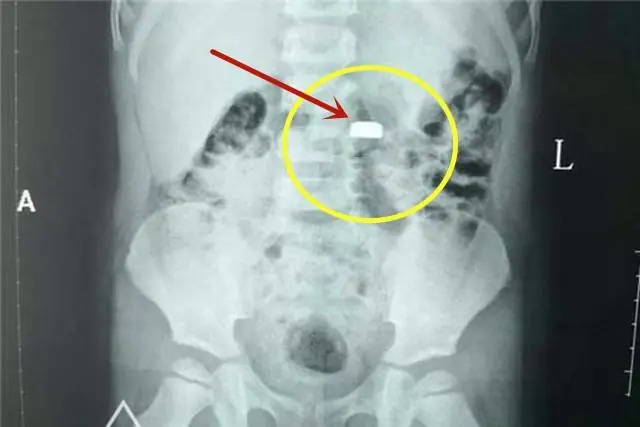

เมื่อถึงโรงพยาบาล แพทย์ตรวจพบว่าเด็กกลืนแบตเตอรี่กระดุมเข้าไปจริง และต้องรีบทำการนำออก โชคดีที่การพามารักษาอย่างรวดเร็วช่วยลดความเสียหายต่อหลอดอาหารได้ทันเวลา